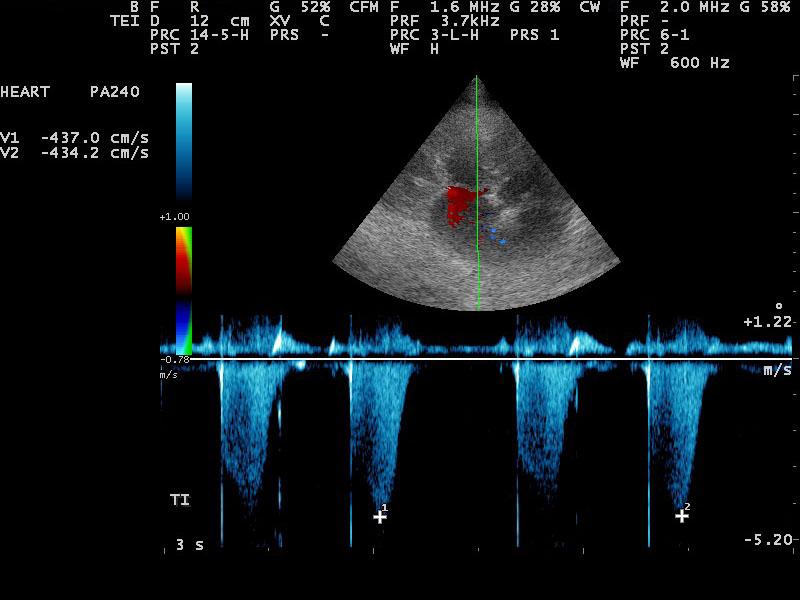

A 10-year-old SF Labrador was presented for evaluation of ascites, which was quantified as a modified transudate. Additional history on this dog was that 11 months prior an ovariohysterectomy and resection of mammary gland tumors had been done. The tumors were benign on histopathology. On abdominal ultrasound, the ascites, hepatic congestion, and a dilated CVC were present.